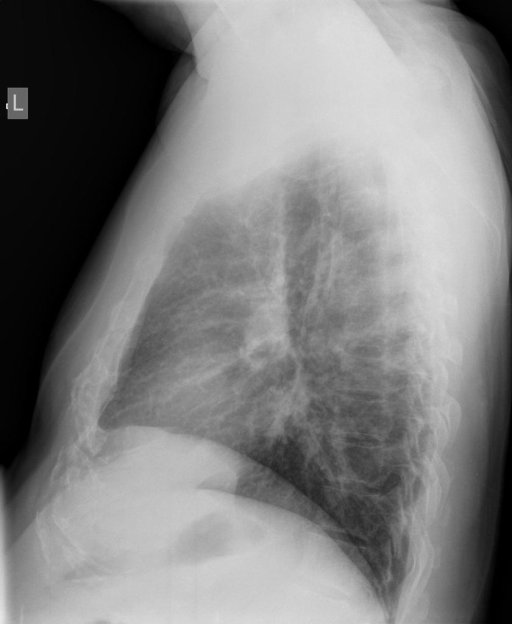

We compare our projected X-Rays with samples from the OpenI dataset for frontal and lateral views in Figure 5. The differences in the frontal view are due to the different positioning of the shoulder girdle. In the X-Rays, the arms are usually placed alongside the body, while in the projected images, the arms are raised due to the nature of the CT scan. In the lateral view, the X-Rays show a more comprehensive range of orientation and pose. However, the projected images, typically taken while the patient is lying down, result in similar poses between the different images. This leads to visual differences between images of female patients in both frontal and lateral views, such as the third column and second row of real X-Ray images and the first column and second row of projected images.